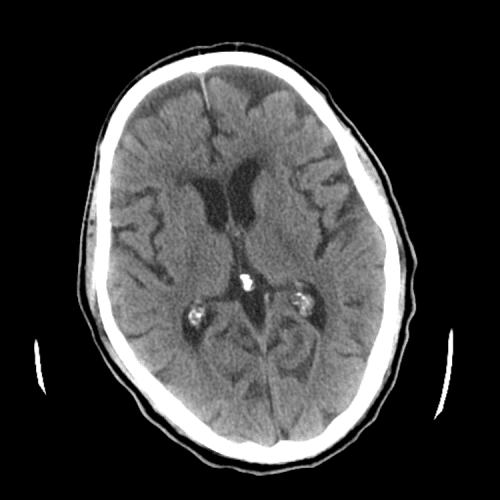

ACA and MCA territory infarct

PCA infarct